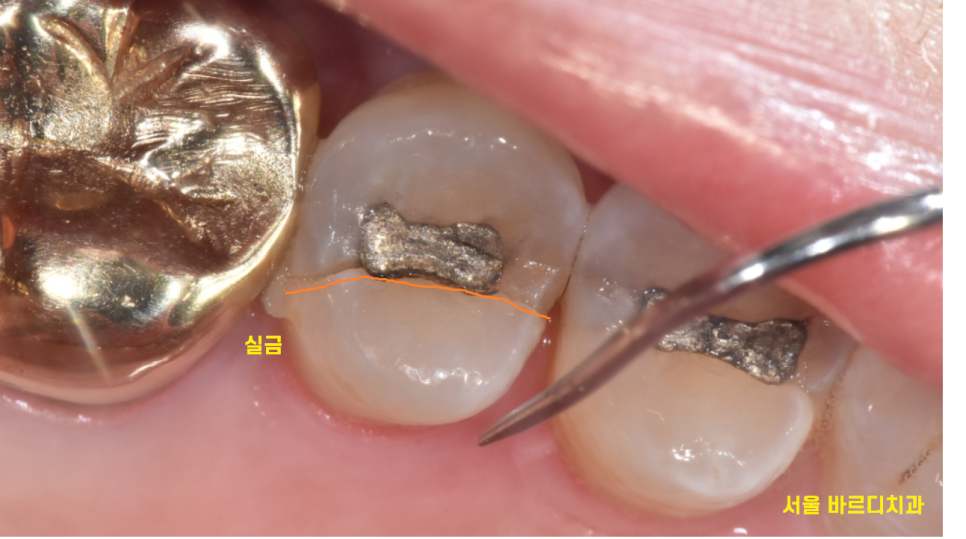

이런..!

치아 실금이 발생했습니다.

이것은 전형적인 crack 치아가 있을 때 증상인데요.

씹을때마다 치아가 벌어지면서 아픈것이죠~